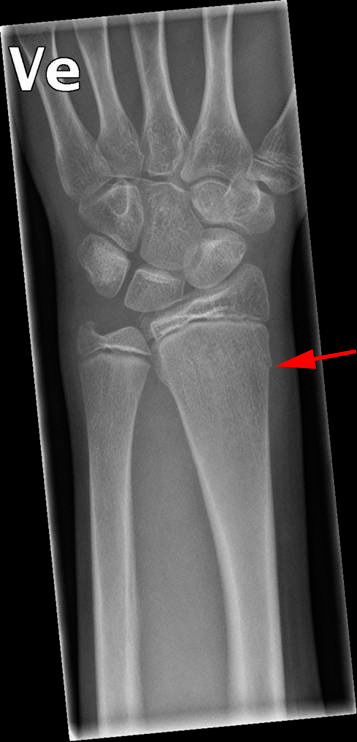

Greenstickfraktur af den store underarmsknogle (radius)

Såkaldt grenfraktur af den store underarmsknogle (radius). Barken er er knækket (rød pil), mens knoglebjælkerne har holdt.